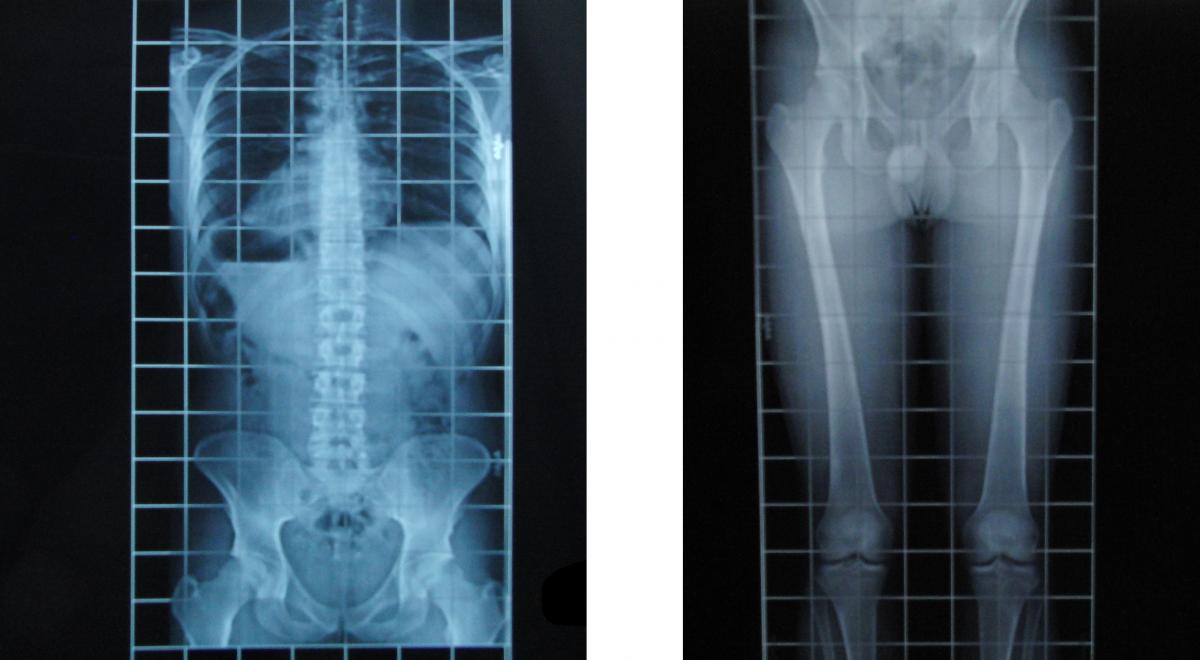

- En los casos necesarios solicitamos una Telemetría. Se trata de una radiografías a escala desde pelvis a pies que nos permiten valorar y cuantificar la disimetría exacta, aunque es importante tener en cuenta que esta prueba no es fiable para valorar rotaciones de la cadera ya que se trata de una estructura en 3D y la radiografía nos da una imagen en 2D, lo que puede dar lugar a algunos errores de medida (al aparecer con mayor tamaño las estructuras que se encuentran más adelantadas).

- Telemetría (radiografías), que muestra una disimetría de 1,3 cm más corto el miembro inferior derecho.